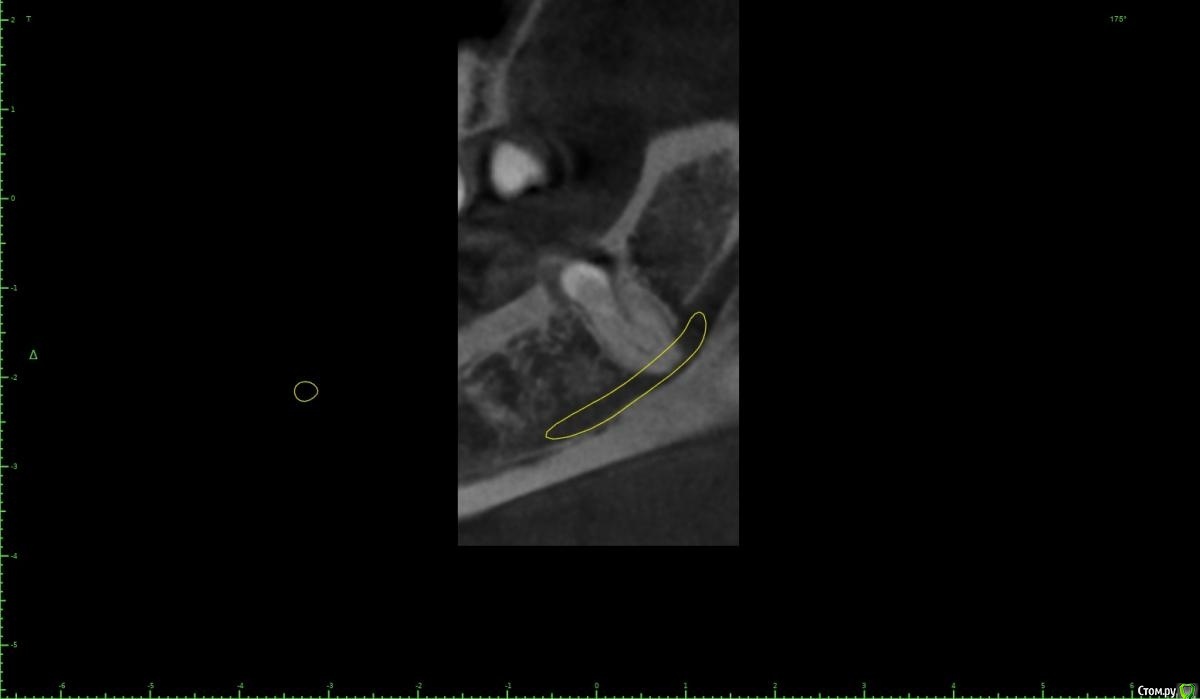

zumanok Опубликовано 15 февраля, 2021 Поделиться Опубликовано 15 февраля, 2021 Коллеги достаточно часто встречаюсь с такой картинкой на КТ в области ментального отверстия . Считаете ли вы это частью тройничного нерва или не обращать внимания? Ссылка на комментарий

Doctor Vlad Опубликовано 15 февраля, 2021 Поделиться Опубликовано 15 февраля, 2021 Коллеги достаточно часто встречаюсь с такой картинкой на КТ в области ментального отверстия . Считаете ли вы это частью тройничного нерва или не обращать внимания там что угодно может быть, больше похоже на пору кости. в этом случае до канала далеко. вы же не собираетесь так глубить? Ссылка на комментарий

zumanok Опубликовано 15 февраля, 2021 Поделиться Опубликовано 15 февраля, 2021 (изменено) там что угодно может быть, больше похоже на пору кости. в этом случае до канала далеко. вы же не собираетесь так глубить?Интересно может быть такая форма канала или стоит взять винт подлиньше? Примерно так и собирался, мб на пол мм выше. Объясните пожалуйста почему не стоит? Кроме того что коронка на 1 мм подлиньше будет. Изменено 15 февраля, 2021 пользователем zumanok Ссылка на комментарий

Doctor Vlad Опубликовано 16 февраля, 2021 Поделиться Опубликовано 16 февраля, 2021 Интересно может быть такая форма канала или стоит взять винт подлиньше? Примерно так и собирался, мб на пол мм выше. Объясните пожалуйста почему не стоит? Кроме того что коронка на 1 мм подлиньше будет.скорей всего там нерва нет и это не канал. Но. А если есть)? Ссылка на комментарий

zumanok Опубликовано 16 февраля, 2021 Поделиться Опубликовано 16 февраля, 2021 (изменено) скорей всего там нерва нет и это не канал. Но. А если есть)?Да вот,для этого и выбрал 3.5 на 8.5. Сам склоняюсь к тому что костный рисунок, информации о таком строении нерва не нашел. Думаю в процессе препарирования ложа посмотреть, если будет чувствительность то не лезть дальше.Подскажите чем Вас смутила глубина установки имплантата? Только этим образованием?По КТ 1.5мм до него. Изменено 16 февраля, 2021 пользователем zumanok Ссылка на комментарий

Raystom Опубликовано 16 февраля, 2021 Поделиться Опубликовано 16 февраля, 2021 Там будет не чувствительность, а резкий провал фрезы после определенного момента препарирования, если не отслеживать момент с глубиной, чем напугаете и себя и пациента. По поводу рисунка может быть как и костный рисунок, так и петля нижнелуночкого канала, зачем проверять? Ссылка на комментарий

Doctor Vlad Опубликовано 16 февраля, 2021 Поделиться Опубликовано 16 февраля, 2021 Да вот,для этого и выбрал 3.5 на 8.5. Сам склоняюсь к тому что костный рисунок, информации о таком строении нерва не нашел. Думаю в процессе препарирования ложа посмотреть, если будет чувствительность то не лезть дальше.Подскажите чем Вас смутила глубина установки имплантата? Только этим образованием?По КТ 1.5мм до него.как он нарисован норм, длиннее не стал бы, чтобы запас был. Просто, по вашим фото не совсем видно где канал. иногда и по кт все очень смутно. особенно когда огромные поры. Ссылка на комментарий